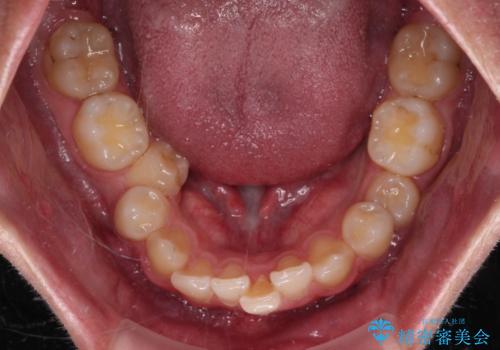

- 「前歯のデコボコが気になる」「前歯の中心がずれていて気になる」とご相談に来られた患者様の症例です。

診察の結果、上下の歯が並ぶためのスペースが不足しており、特に上顎右側の側切歯が内側(口蓋側)に転移していたため、正中が大きく右にずれている状態でした。